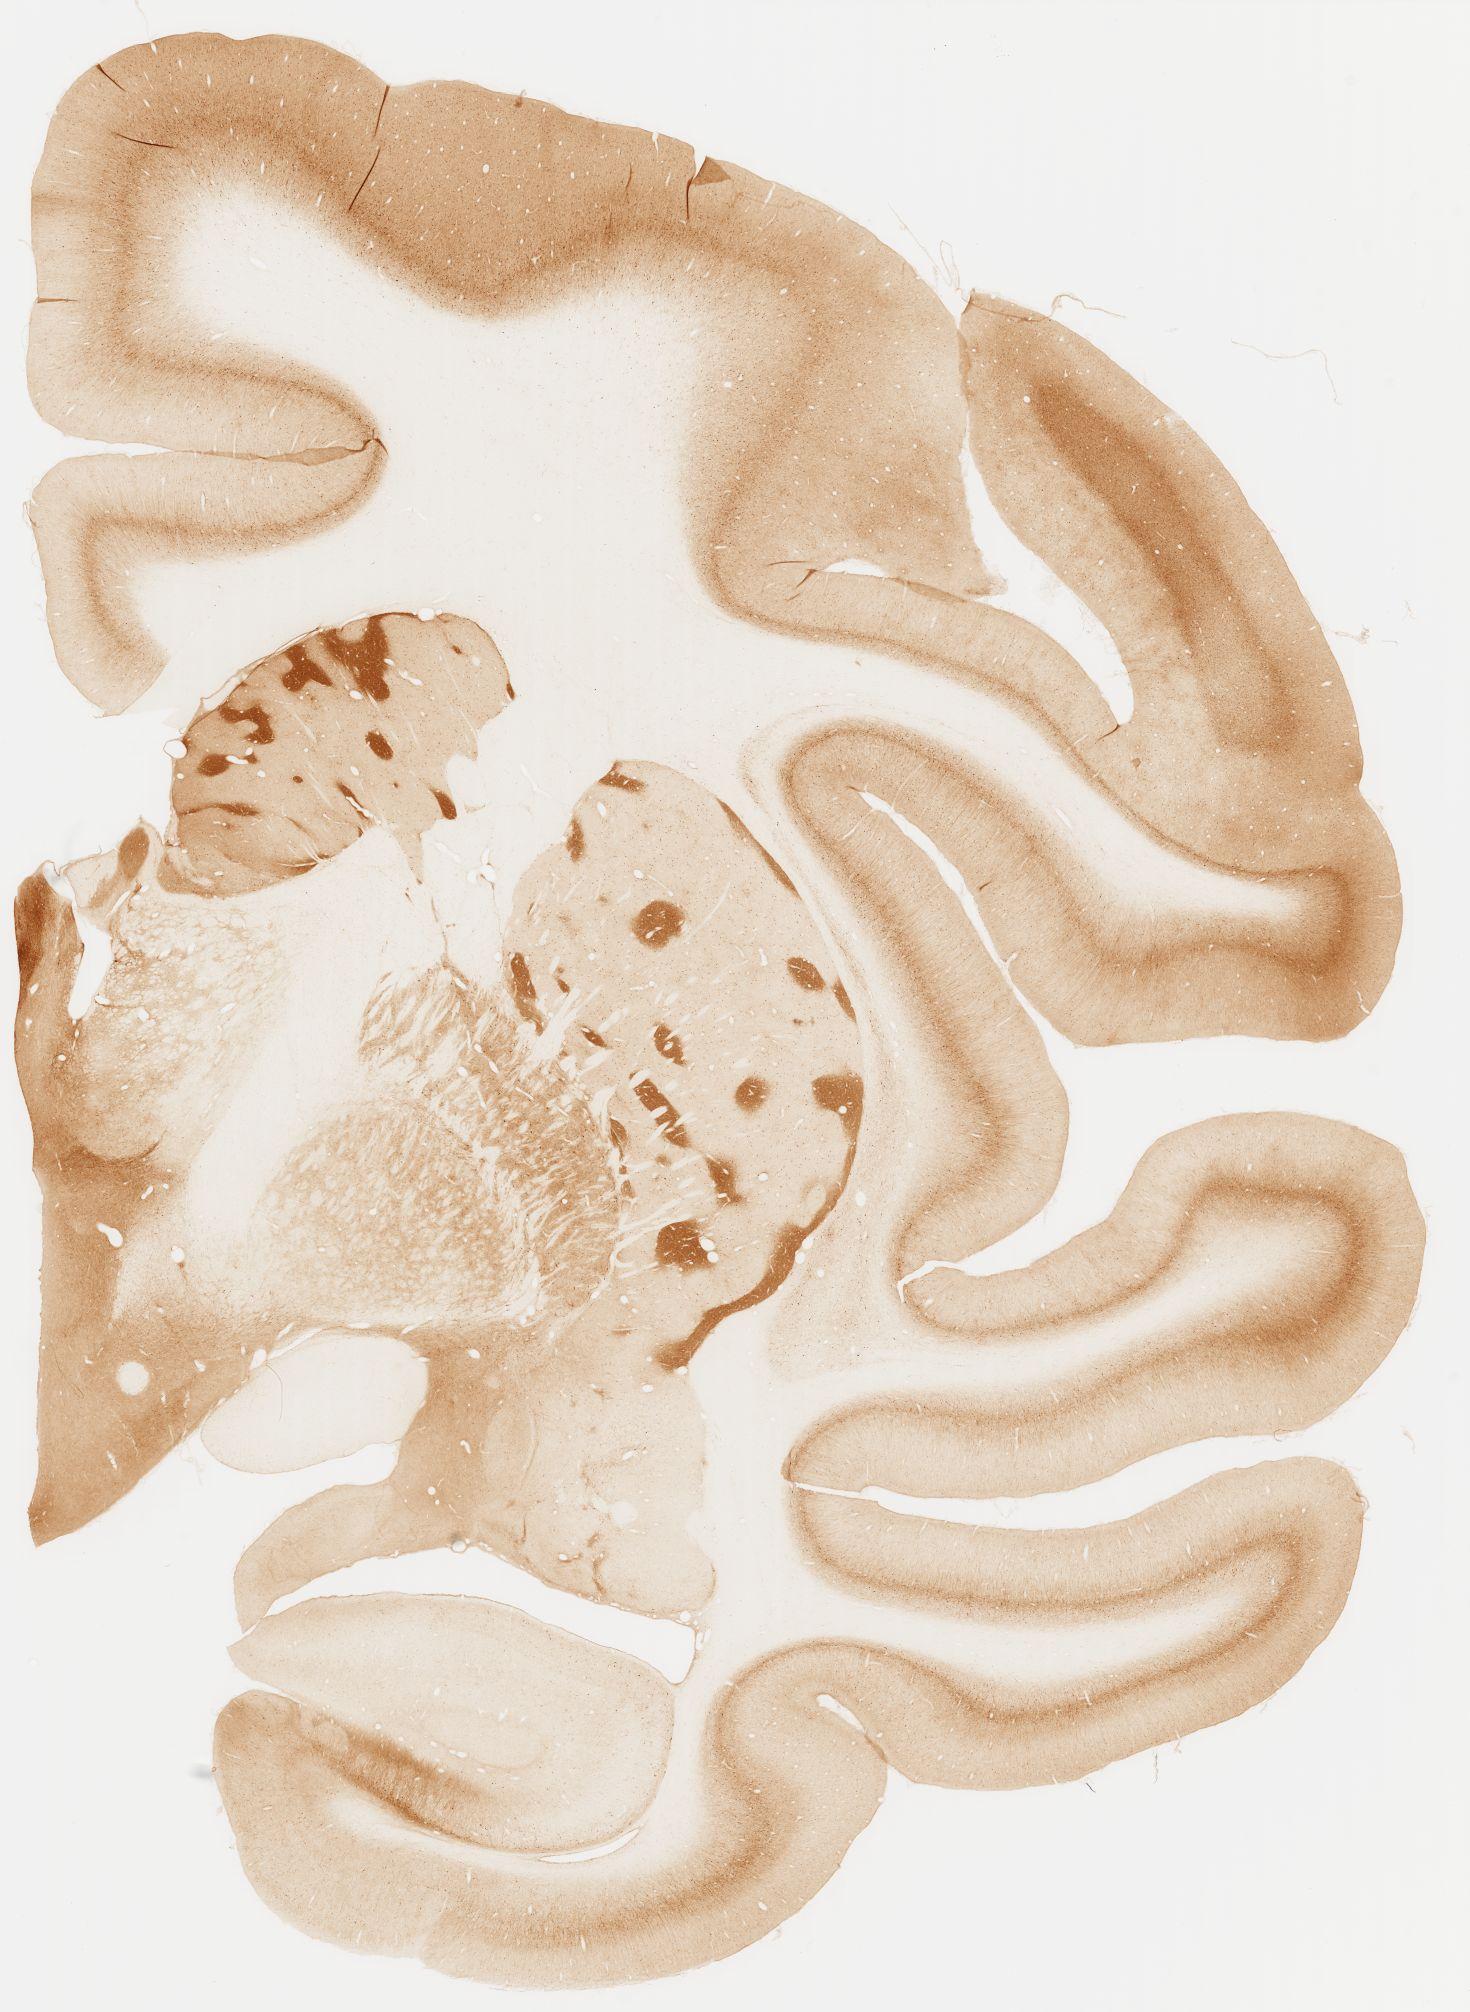

Datasets -> Macaca Fascicularis -> KChIP1, (Potassium Voltage-Gated Channel-Interacting Protein 1), coronal, immuno, Whole-Brain, adult

[ Metadata ]   ·   Source: Edward G. Jones

Displaying Sections 41 thru 80 of 92 Sections for this Dataset